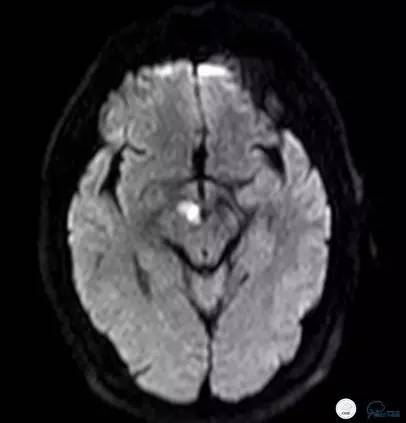

就诊于外院查头颅核磁DWI+MRA(图1-2):中脑右侧及右侧丘脑新鲜脑梗死,椎基底动脉及双侧大脑后动脉未见显影。住院予波立维、拜阿司匹林抗血小板聚集、立普妥降脂治疗后症状无好转,病情逐渐加重。为进一步行血管内治疗来我院。

图1

图2